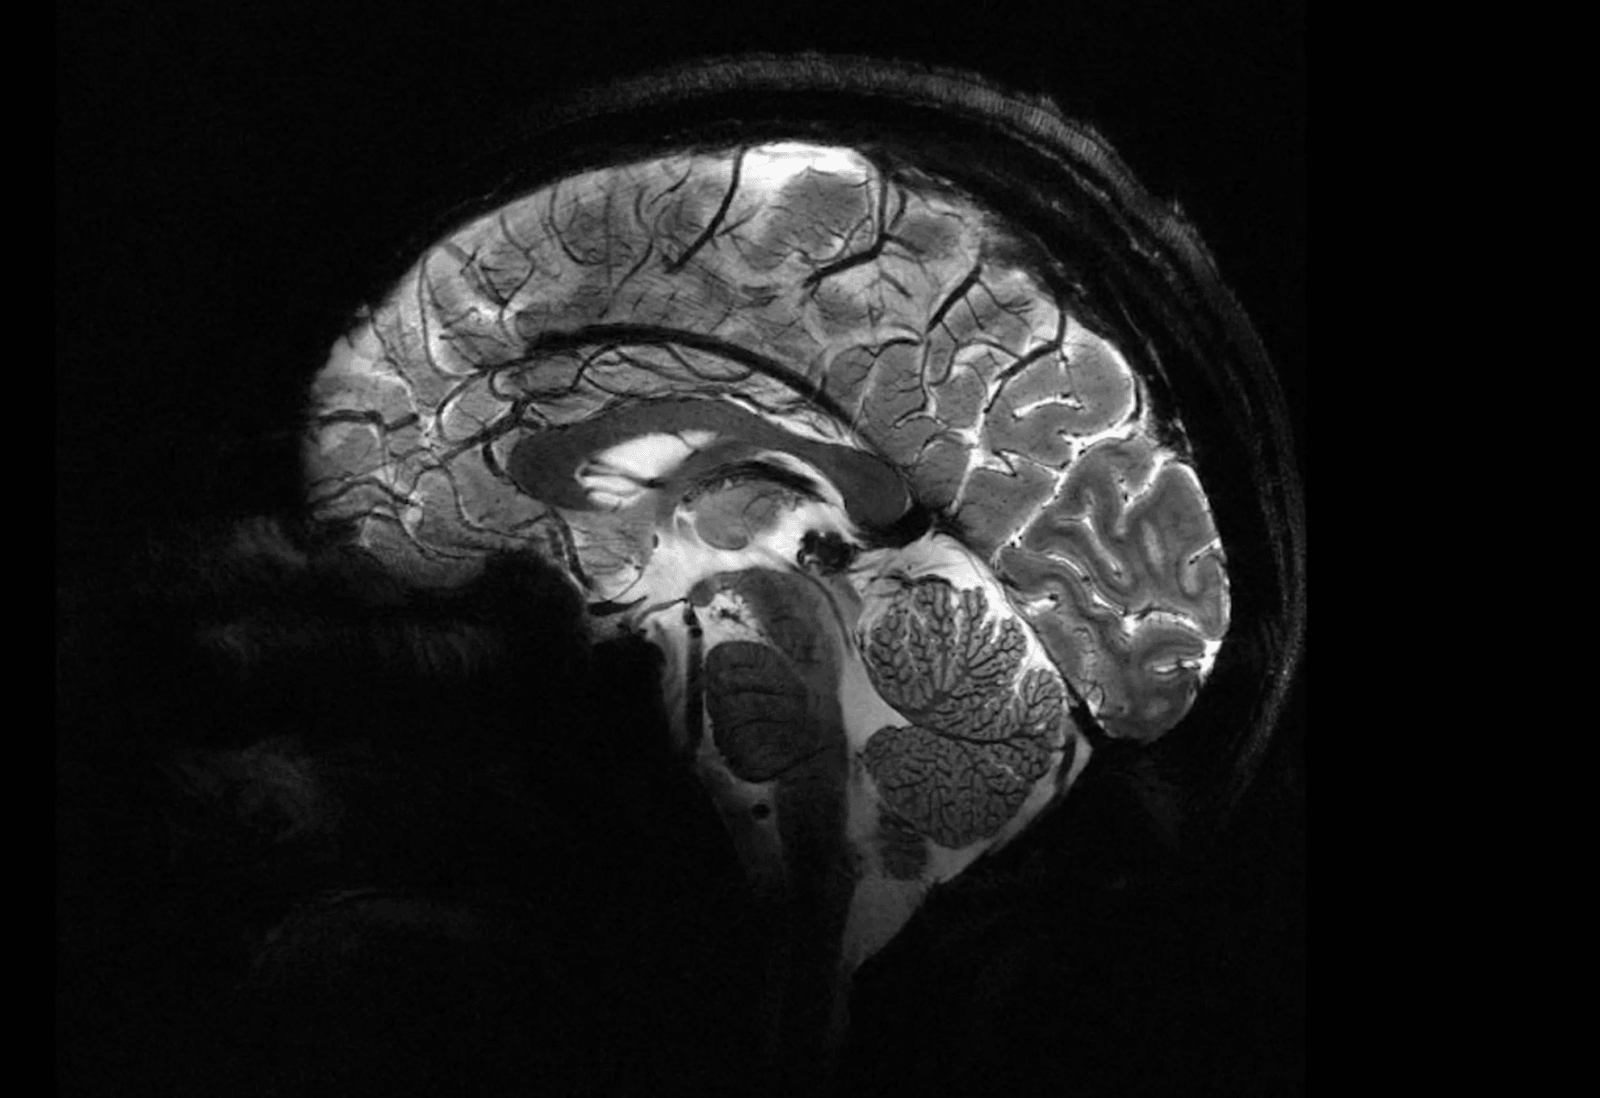

Główną zaletą dodatkowej mocy jest to, że zdjęcia mózgu o znacznie wyższej rozdzielczości można wykonywać znacznie szybciej. W ciągu zaledwie czterech minut Iseult może rejestrować obrazy tkanki mózgowej o grubości do 0,2 mm w poziomie, a w “plasterkach” o grubości zaledwie 1 mm. Aby konwencjonalne aparaty MRI mogły wykonać zdjęcia o takiej rozdzielczości, pacjenci musieliby leżeć w całkowitym bezruchu przez ponad dwie godziny – najmniejszy ruch spowodowałby rozmycie zdjęcia, a to po prostu niewykonalne.

Ludzkie mózgi dokładne jak nigdy wcześniej